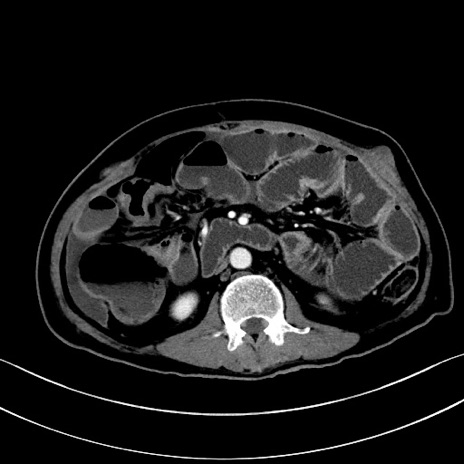

症例28(横断像)

【症例】60歳代男性

【主訴】嘔吐

【現病歴】胃癌にて胃全摘後。食思不振が悪化し、夜中に嘔吐することがある。

【既往歴】胃癌、胃全摘、脾摘、胆摘後

【データ】WBC 5900、CRP 10.56